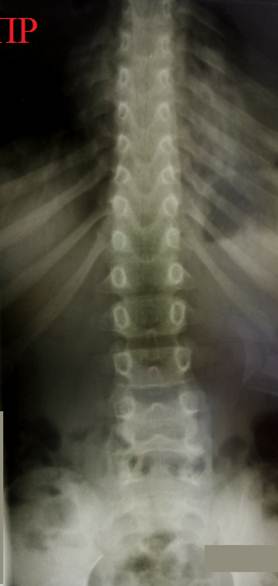

Снимки

позвоночника ребенка с идиопатическим сколиозом в возрасте 12 и 14 лет (справа

– слева соответственно). На снимке в 12 лет определяется компенсированная С - образная

деформация позвоночника в области верхней части поясничного – нижней части

грудного отделов. Признаки ротации позвонков в области дуги – тени ножек дуг

смещены от центральной линии тел позвонков. На снимке в возрасте 14 лет

определяется S - образная деформация

позвоночника, потому что сформировалась компенсаторная дуга 5° в грудном отделе. Смещение теней ножек дуг

относительно центральной линии тел

позвонков стало еще больше, что говорит о том, что структурные изменения в

позвонках увеличились. При этом нарастание угла деформации основной дуги

составило всего лишь 3 градуса.

Интересно, что в конкретном

примере Slide – Shift

и вершина дуги направлены влево.